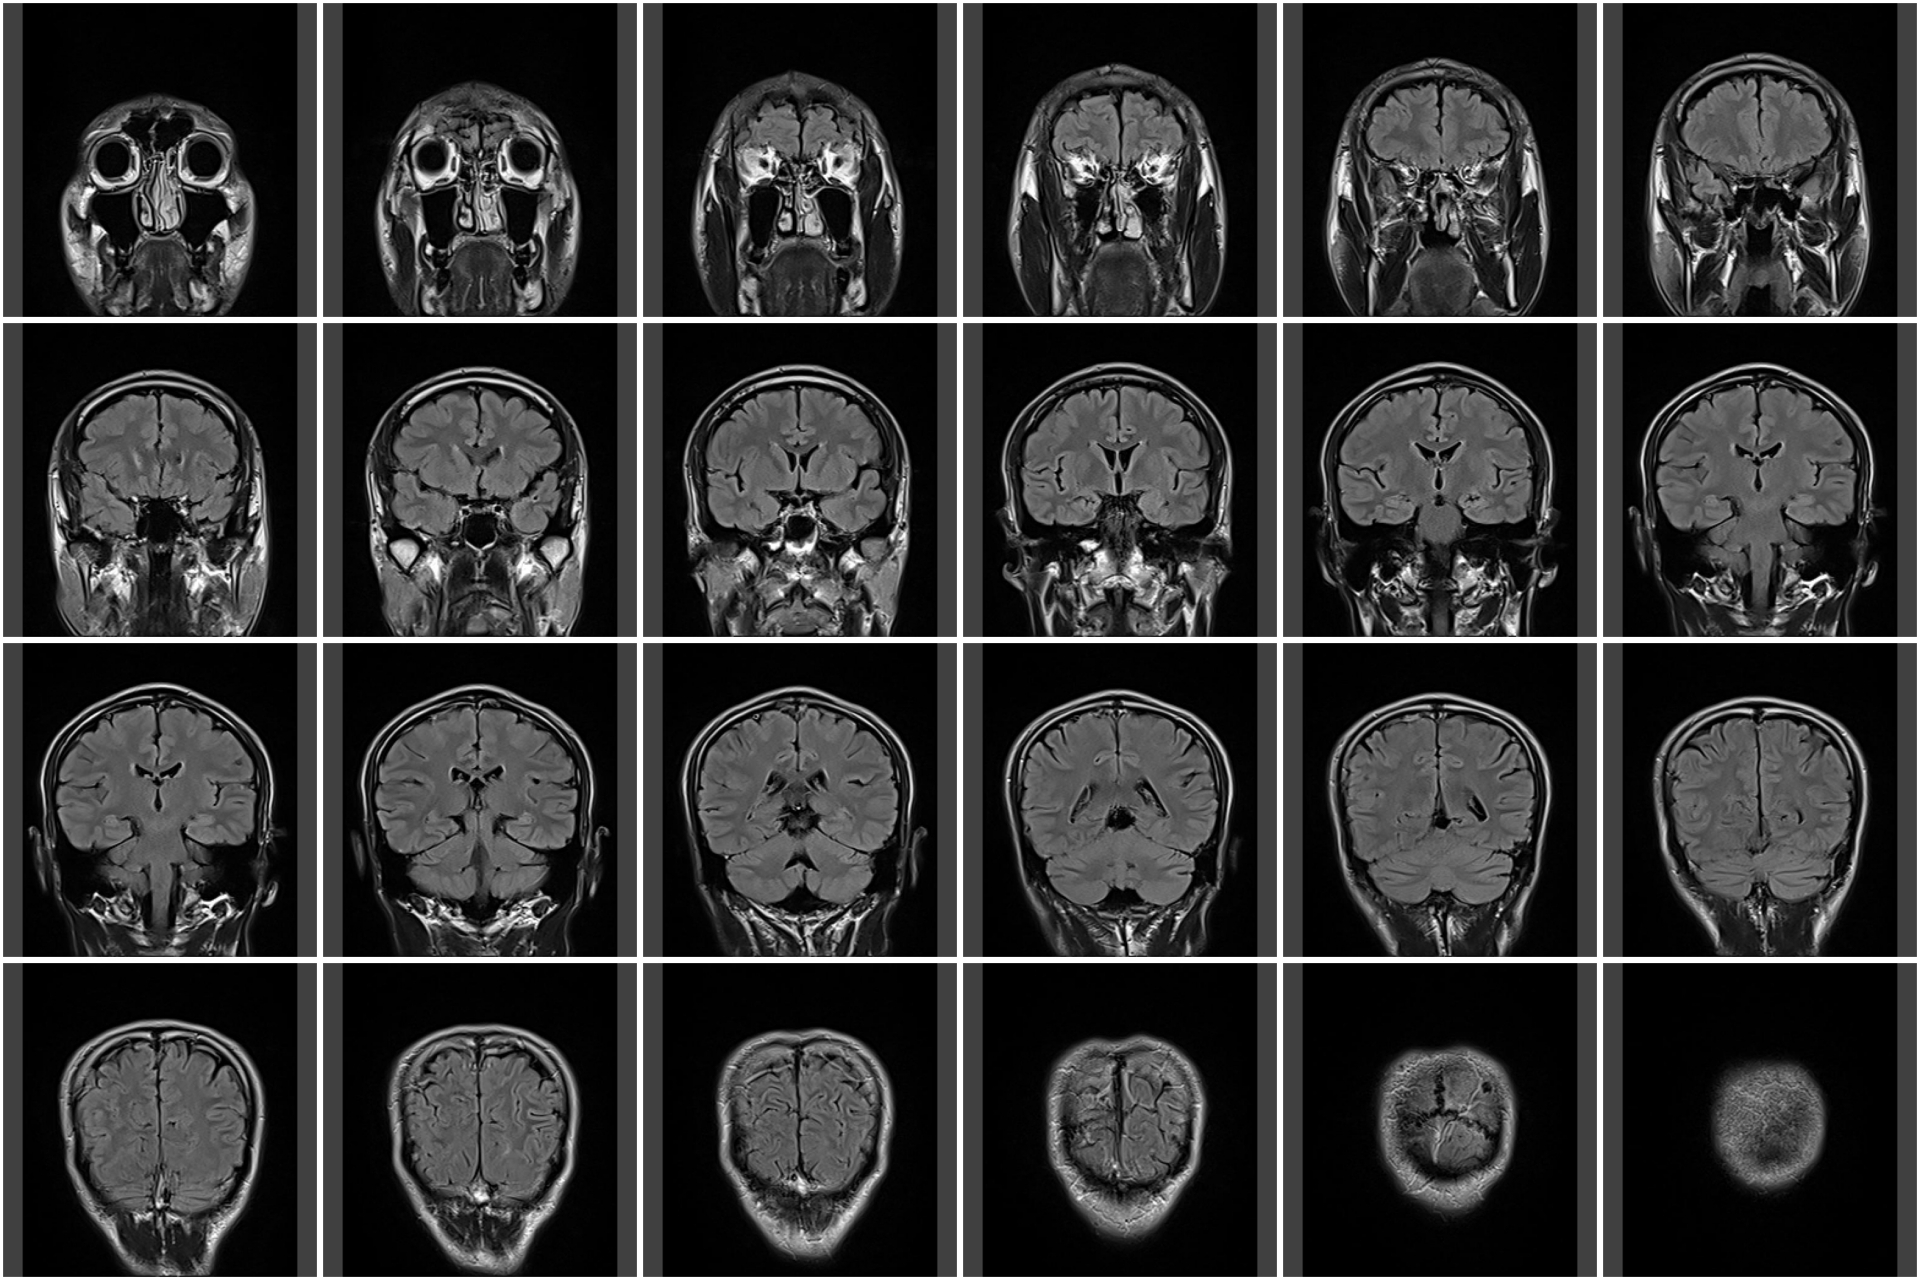

談到存活期,林家瑋表示,得到這種腫瘤存活時間很少超過2年,「目前治療上來說第一個就是手術,手術會盡量想辦法把這個腫瘤拿乾淨,但事實上是拿不乾淨的,因為這種腫瘤在做核磁共振掃描時,會看剪影範圍來決定腫瘤在哪裡,但這種腫瘤特性就是如果你看到一個3公分的腫瘤在腦部,事實上這個腫瘤細胞早就已經超過3公分的範圍,所以只是肉眼看到這3公分腫瘤把它拿乾淨,其實已經跑到腦部其他地方去了。」

林家瑋提到,大部分腫瘤在復發的時候,都是在原發的位置的3公分範圍是最常見。「假想為了減少復發、拿掉3公分的腫瘤,外圍再各加3公分,等於要拿掉9公分的範圍,幾乎半個腦都拿掉了,這樣沒有意義,所以通常碰到這種腫瘤就是盡可能地拿但沒辦法完全拿乾淨,沒有拿乾淨的部分就要配合其他治療。」